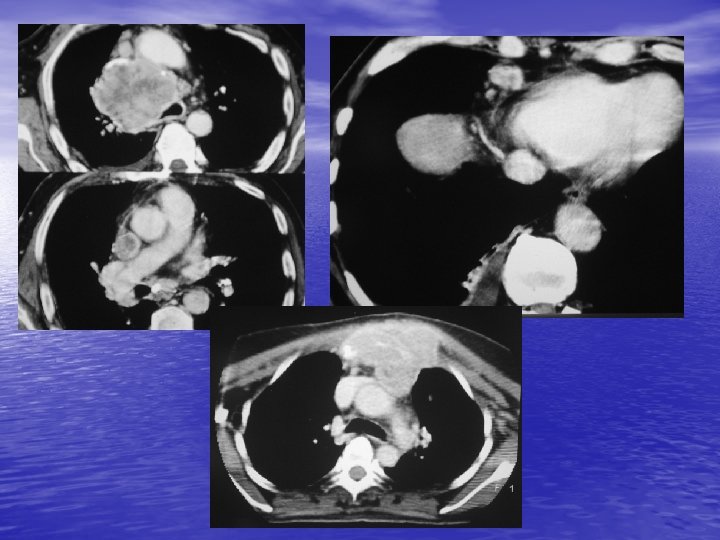

2. 2. TDM - Reconnaissance de la nature vasculaire d’une masse médiastinale. - Détection de petites tumeurs (supérieure au cliché rx thoracique). - Localisation des tumeurs : 8 compartiments. - Reconnaissance du contenu de la tumeur : hypervascularisation (goitre, thymome, adénome parathyroïdien, paragangliome, …) calcifications inconstantes (goitre, ADP, thymome, tumeurs nerveuses, …), liquidiennes (kystes dérivés de l’intestin primitif, lymphangiome, thymome), graisseuse (lipome, liposarcome).

- Recherche de signes de malignité : lésion mal - limitée, densification de la graisse. Bilan préopératoire. Guidage d’une biopsie.

3. 2. Autres tumeurs - Tumeurs germinales (tératome, carcinome embryonnaire). - Adénome parathyroïdien. - Lymphangiome kystique. - Kyste pleuro-péricardique. - Goitre plongeant. - Pseudo tumeur graisseuse (par hernie diaphragmatique antérieure), vasculaire (anévrysme de l’aorte ascendante ++), cardiaque.